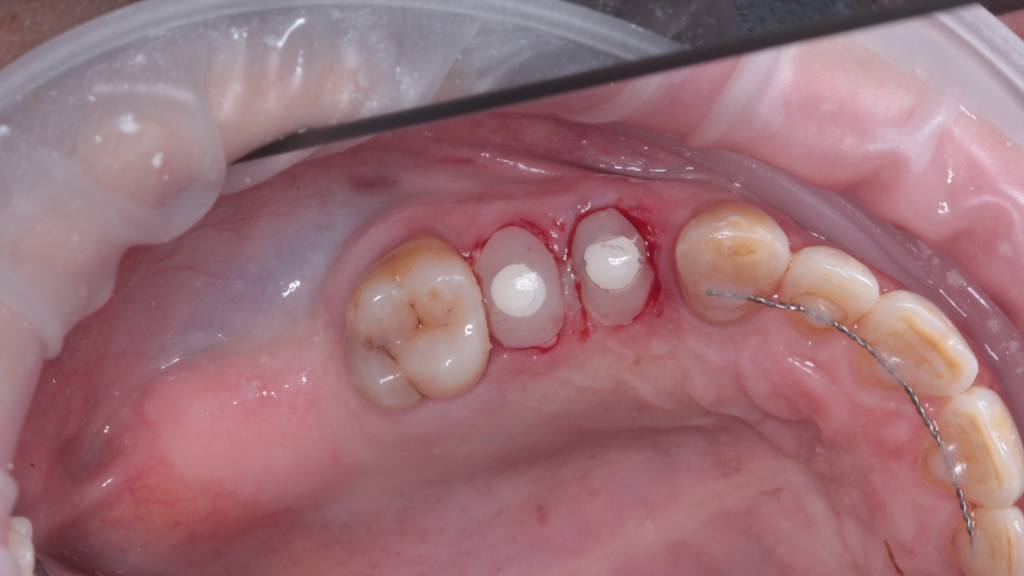

Одномоментная имплантация Impro с установкой временного абатмента

Описание клинического случая:

• Атравматичное удаление зуба 2.4, 2.5

• Одномоментная дентальная имплантация IMPRO

• Использование фибриновой мембраны Clot-PRF

• Установка временного абатмента IMPRO

• Изготовление индивидуального формирователя десны

Клинический случай Узденовой Зульфы Альбертовны